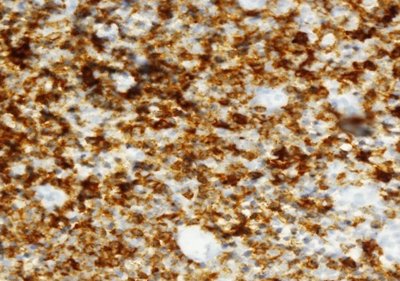

La inmunohistoquímica confirmó la afectación cutánea por leucemia linfocítica crónica. Los linfocitos pequeños con contornos nucleares irregulares mostraron una fuerte positividad para marcadores de células B CD20 (Figura 3), CD79, CD5, CD23 (Figura 4), y LEF-1 con tinción negativa para CD3, CD10 y ciclina D1.

Figura 3: Linfocitos B